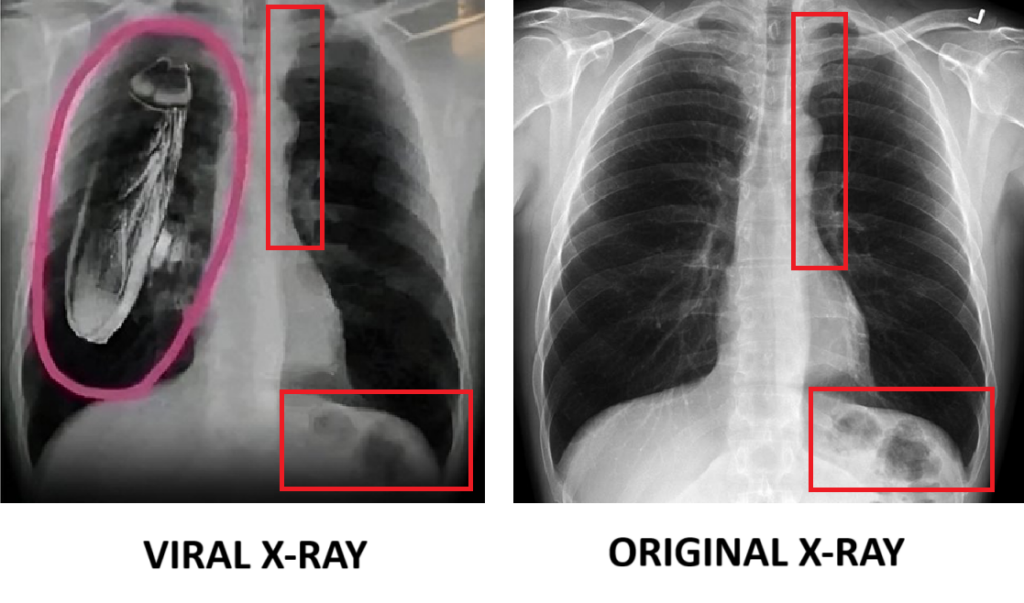

दावे की पड़ताल में संबंधित कीवर्ड की मदद से गूगल सर्च करने पर हमें ऐसी कोई मीडिया रिपोर्ट नहीं मिली। इसके बाद वायरल एक्स-रे की तस्वीर को रिवर्स सर्च करने पर यह तस्वीर हमें Radiopaedia नाम की वेबसाइट पर पोस्ट मिला। लेकिन इस तस्वीर में कॉक्रोच नहीं है। वेबसाइट के मुताबिक यह 50 साल के पुरुष की छाती का एक नॉर्मल एक्स-रे है।

पड़ताल में आगे हमने वायरल एक्स-रे और असल एक्स का आपस में मिलान किया तो पाया कि दोनों एक्स- रे एक ही हैं। जिससे स्पष्ट हुआ कि इस एक्स-रे को एडिट कर इसपर कॉक्रोच की तस्वीर को जोड़ा गया है।